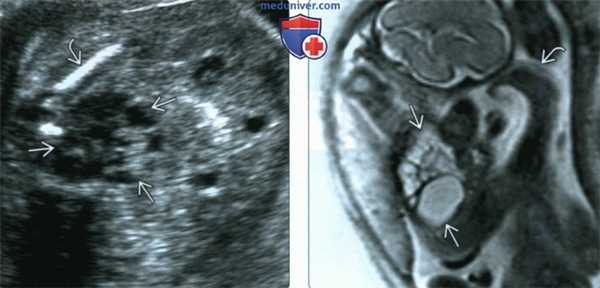

(Слева) УЗИ в поперечной плоскости. Почка с МКДП значительно увеличена выходит за срединную линию и граничит с передней брюшной стенкой. Внимание обращает соотношение размеров с нормальной почкой (калиперы). Почки с МКДП увеличиваются во внутриутробном периоде, но атрофируются после рождения ребенка.

(Слева) УЗИ малого таза плода, поперечная плоскость. Визуализируется сложное кистозное образование, прилежащее к подвздошному гребню - эктопическая почка с МКДП. Показаны дополнительные исследования.

(Справа) МРТ одного из плодов двойни. МКДП с агенезией противоположной почки. Выраженная кистозная дисплазия и косолапость, развившаяся из-за малово-дия. МРТ помогает в случае трудного диагноза. Также ее используют, когда требуется исследовать большой объем тканей, как при данной многоплодной беременности.